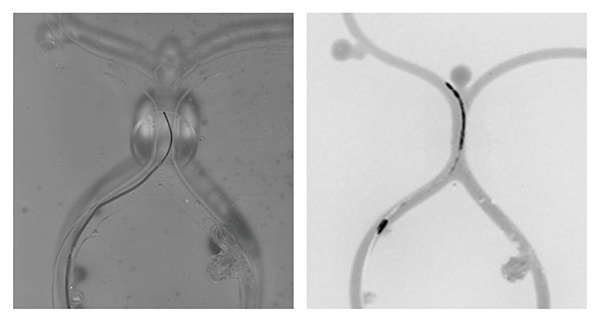

図1 血管モデルの可視光による画像(左)と非被ばく血管内治療シミュレータによるX線模擬画像(右)

可視光による画像(左)は立体感があり、奥行き方向の位置関係が分かるので、実際のX線画像より操作が容易になってしまう。今回開発した装置の画像(右)は平坦でX線画像に近い。

横田TLと深作客員研究員らが開発したトレーニング装置では、生命科学研究などでよく用いられる「蛍光観察技術」を利用した。透明な血管モデルを用意して、カテーテルの先端などに蛍光色素を付け、人工血管にも同じ蛍光色素を薄めた液を満たした。蛍光色素が発する光だけを通すフィルターを装着したカメラで撮影したところ、X線透視に近い平坦な画像を再現できたという(図1)。